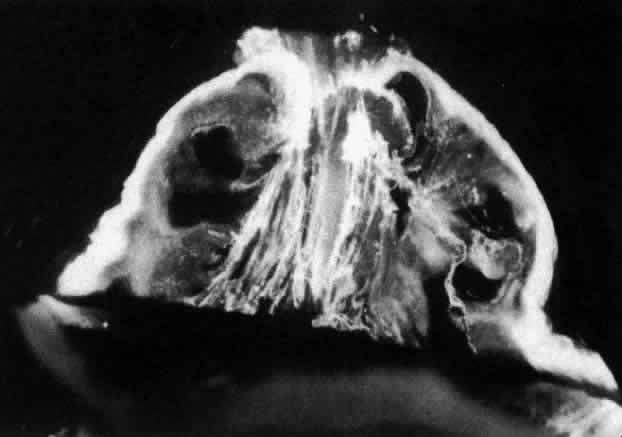

Fig. 7. Although centrifuged to concentrate structural elements, this human vitreous specimen contains no membranes or membranous structures. Only collagen fibrils were detected. There were also bundles of parallel collagen fibrils such as the one shown here in cross section (arrow). (Sebag J: The Vitreous--Structure, Function and Pathobiology. New York, Springer-Verlag, 1989)

Ultrastructural studies90 have demonstrated that collagen organized in bundles of packed, parallel fibrils (Fig. 7) is the only microscopic structure that could correspond to these fibers. It has been hypothesized that the visible vitreous fibers form when HA molecules no longer separate the microscopic collagen fibrils, resulting in the aggregation of collagen fibrils into bundles from which HA molecules are excluded.82,92 Eventually the aggregates of collagen fibrils attain sufficiently large proportions that can be visualized in vitro (see Figs. 4 THROUGH 6) and clinically. The areas adjacent to these large fibers have a low density of collagen fibrils in association with HA molecules and therefore do not scatter light as intensely as the larger bundles of aggregated collagen fibrils. Furthermore, these adjacent areas offer relatively little resistance to bulk flow through vitreous, since they are largely occupied by hydrated HA.